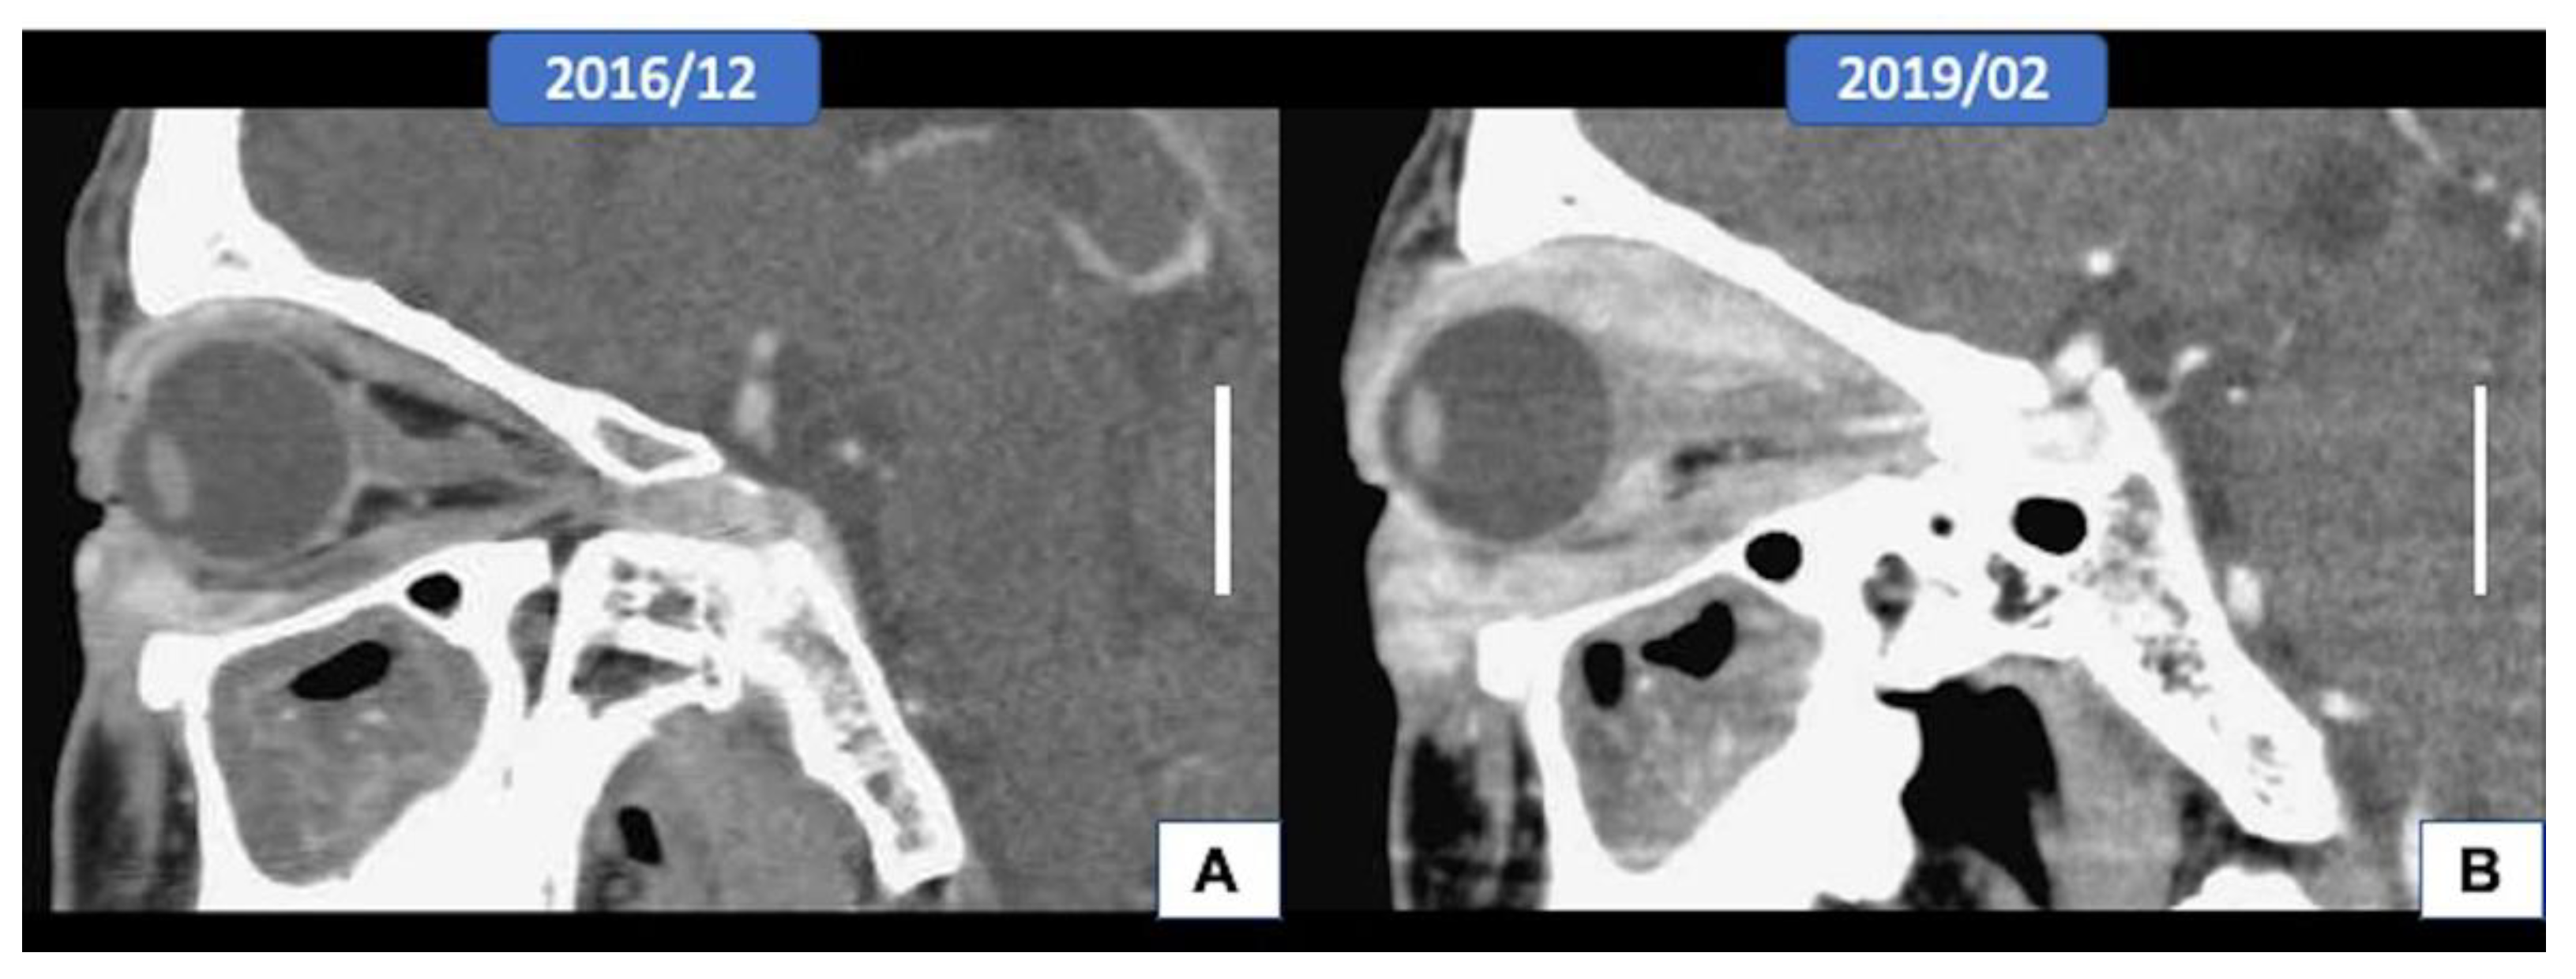

3.1. Clinical Features